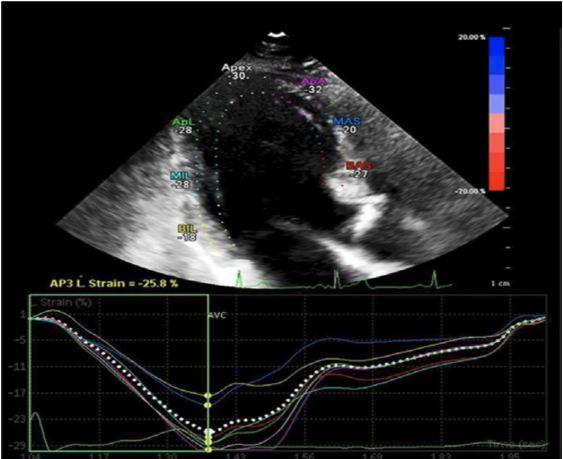

LV dp/dt:800~1200 mmHg/s。除外整体的收缩力的评价,我们也可以通过目测对左室单一节段的心肌收缩力进行分析。若出现明显的局部异常运动,我们可以选择一维的组织多普勒技术(TDI)对特定节段的运动采集数据进行分析(相关内容前次文章已经阐述)。若设备条件支持,我们可以选择二维层面的斑点追踪技术(STI)对局部心肌的运动做分析,可以获得目标节段的定量应变数值和应力数值,描记出心肌的应变-时间曲线,从而对心脏的局部运动做更详细的分析。相关示意图如图8所示。

图8 左心室分节段心肌运动斑点追踪示意图

一般而言,我们会分别采集各个节段的应变结果,汇总形成牛眼图(图9),得出全局的应变值。不同的设备获取的数据会有所差别,详细的临界数值还需要结合设备进行详细解读。

图9 左心室分节段心肌运动斑点追踪二维成像应变测量汇总示意图(牛眼图)